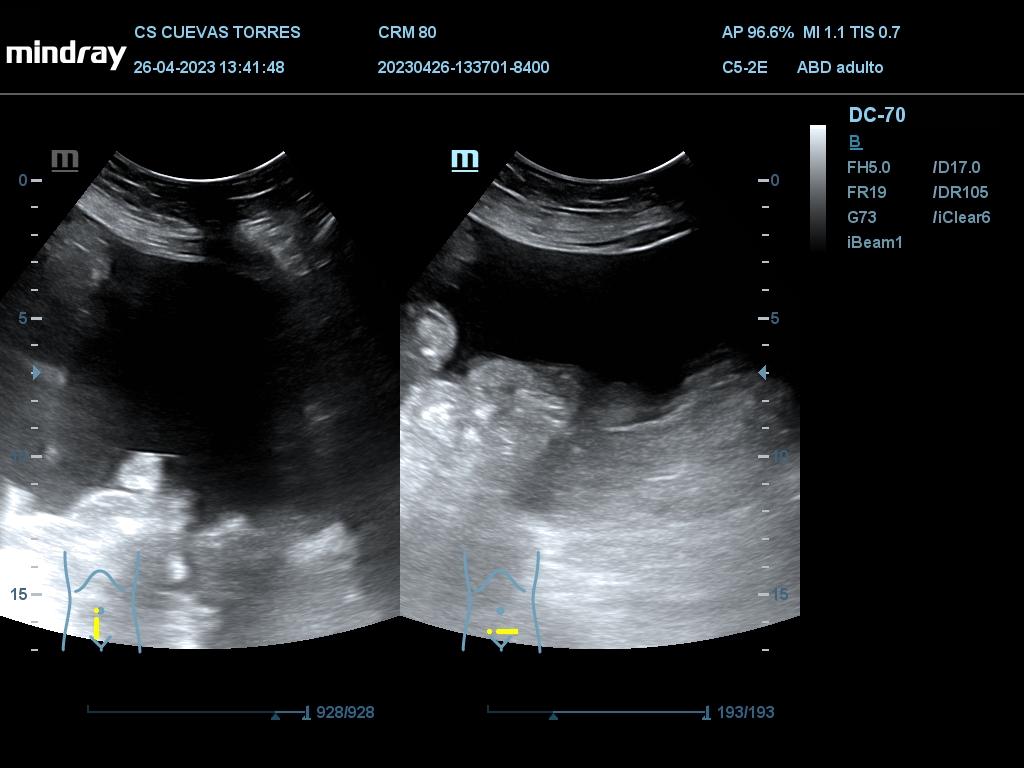

En la ecografía clínica observamos claramente la presencia de líquido libre desde el comienzo de la exploración. Continuando con el estudio Visualizamos circulación portal turbulenta y en el rastreo hepático una lesión ocupante de espacio (LOE) con captación Doppler de 7,45 cm de diámetro máximo.